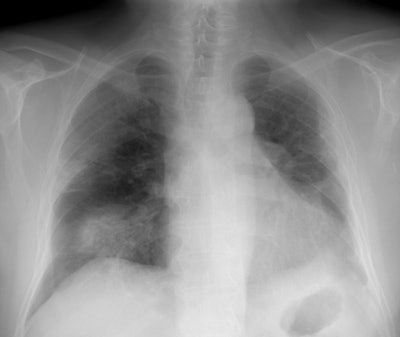

Following antibiotic treatment, the infiltrates and the patients symptoms had worsened (Click image to enlarge)

Chest CT revealed patchy areas of parenchymal consolidation with air bronchograms. Post radiation changes are seen in the left lung. Lung biopsy confirmed the diagnosis of BOOP. BOOP has been described in the contralateral lung following radiation therapy [Respir Medicine 1997; 91: 241-244]. The patient responded to steroid therapy.